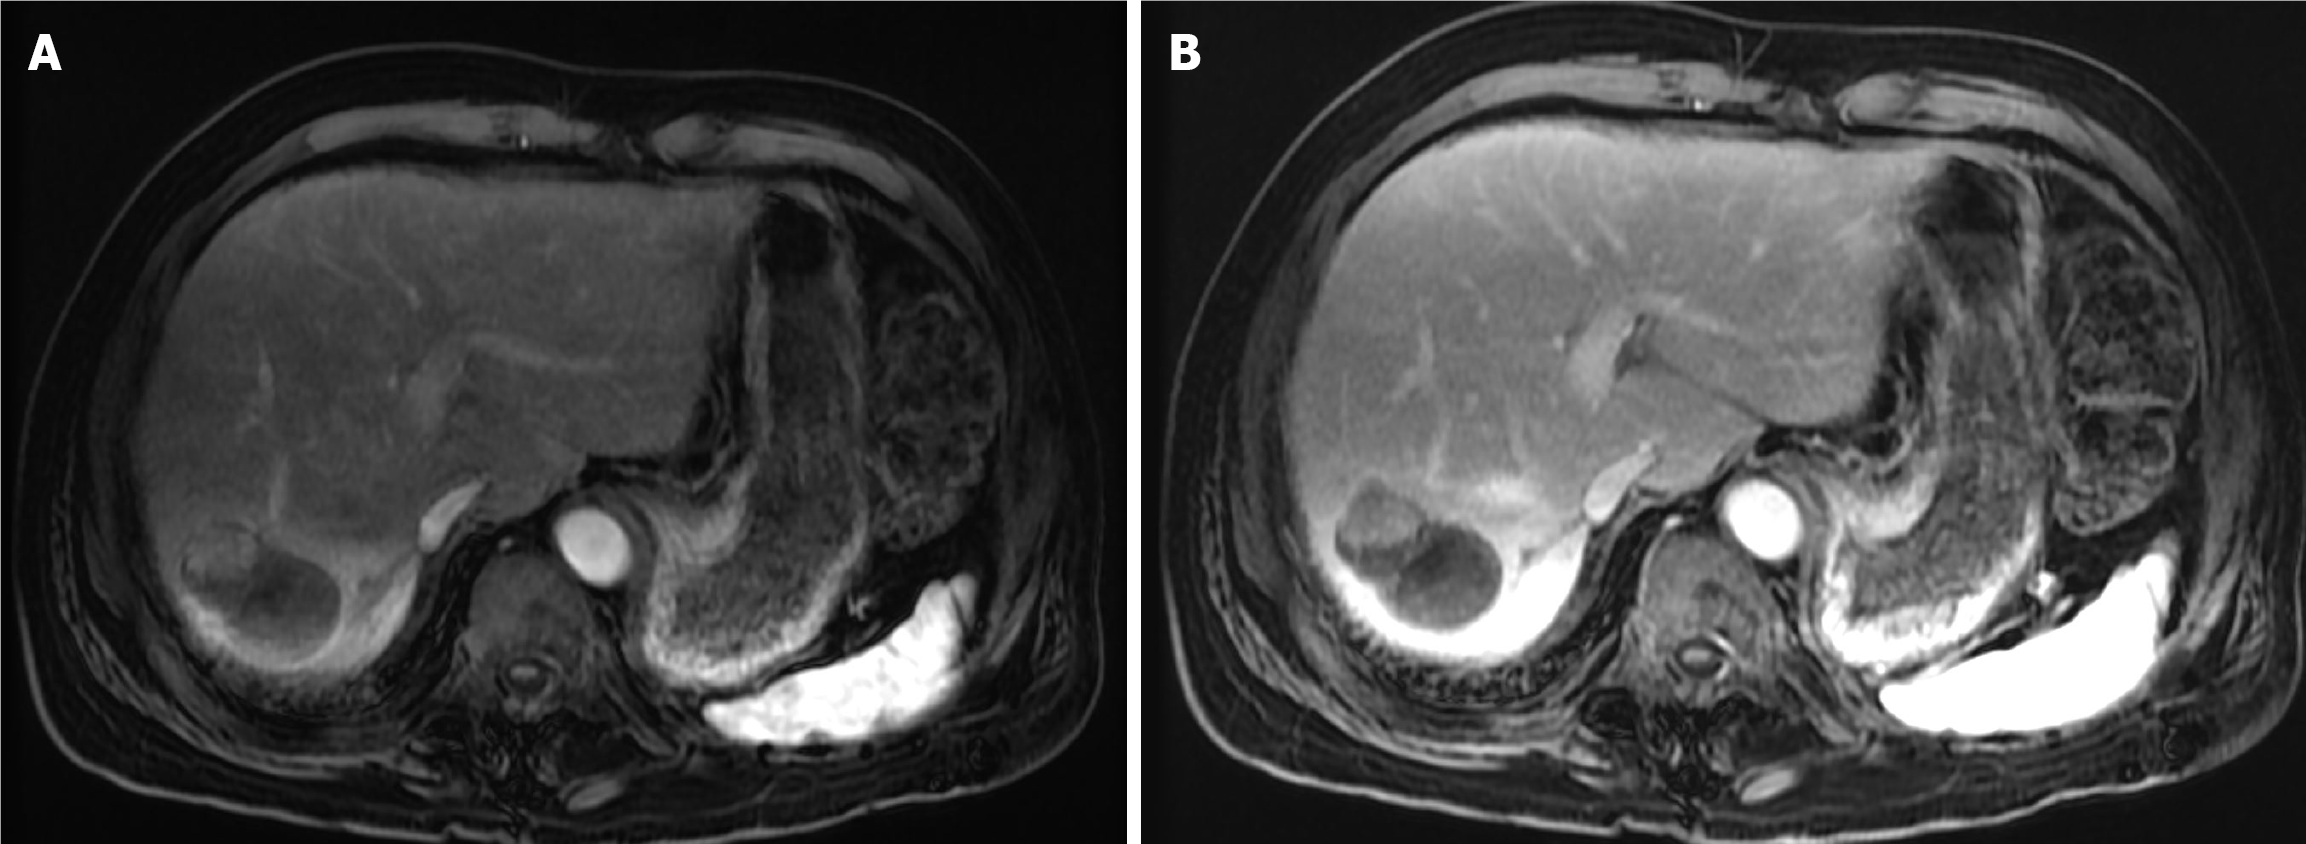

Figure 9 Eight-week follow-up magnetic resonance imaging of the abdomen after the first drug-eluting bead transarterial chemoem bolization in Case 2.

A: Arterial phase magnetic resonance imaging showed a residual hypervascular nodule at the periphery of the treated mass, indicating partial response; B: Delayed phase magnetic resonance imaging demonstrated washout of the residual soft tissue nodule.